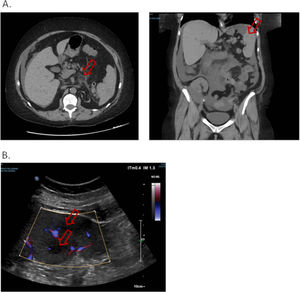

Five days later, she presented to emergency department for abdominal pain. The patient was afebrile, the abdomen flexible. A new non-injected CT scan was performed and found migration of the digestive inflammation site that resulted in duodeno-jejunitis with regression of the right ileocolitis, and a large peritoneal effusion was observed, as well as multiple hypodense splenic lesions, the largest being measured at 30 mm in the lower pole (Fig. 2.A.). The examination was supplemented by a doppler ultrasound which showed hypoechogenic and non-vascularized lesions, some of which presented a target appearance suggestive of candida abscess according to the radiologist's interpretation (Fig. 2.B.). The patient was admitted once more to the nephrology department. A gastroscopy was performed, with no macroscopic characterized abnormality outside atrophic gastritis, and gastric and duodenal biopsies performed came back sterile on standard culture and Sabouraud medium. Six blood cultures were taken and remained sterile, including one before any antibiotics. Empirical treatment was introduced with 4 g of intravenous piperacillin + tazobactam three times a day for 14 days, and oral fluconazole (800 mg on the first day then 200 mg once a day) for six weeks, with adjustment of the dosage of tacrolimus. An abdominal ultrasound examination was performed after the antibiotic treatment, which found a total regression of splenic lesions and peritoneal effusion. The patient was discharged.

A. Non-injected abdominopelvic scan. Duodeno-jejunitis with heterogeneous circumferential wall thickening and densification of fat around the duodenojejunal frame. Peri hepato-splenic, inter-anses, parietal-colic gutters and pouch of Douglas peritoneal effusion of great abundance. Multiple hypodense splenic nodules. B. Splenic Doppler ultrasound. Non-vascularized hypoechoic lesions with Doppler energy, some with a target appearance.